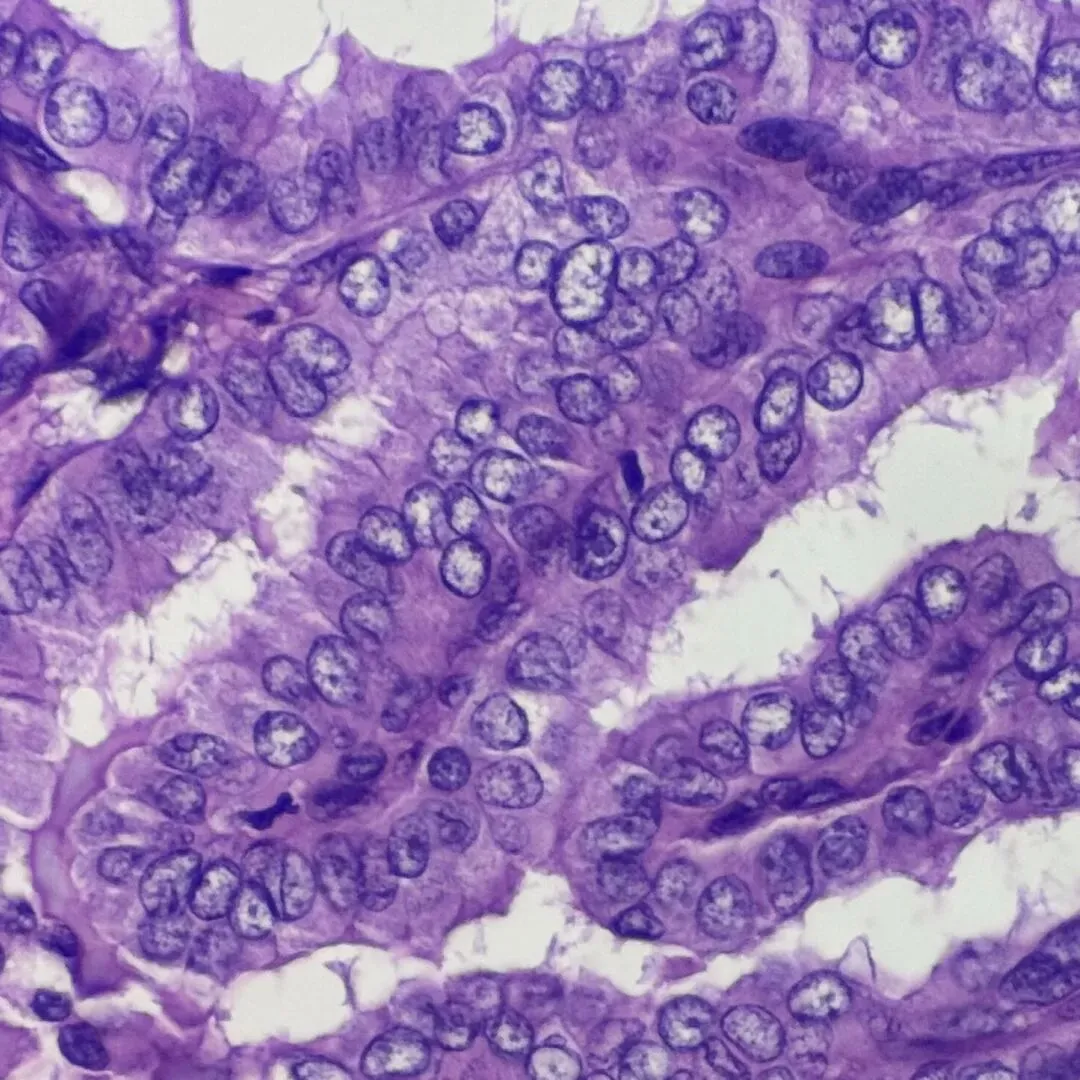

图3

图3-4 组织学:可见含纤维血管轴心的乳头,毛玻璃样核,核拥挤重叠,核沟易见。